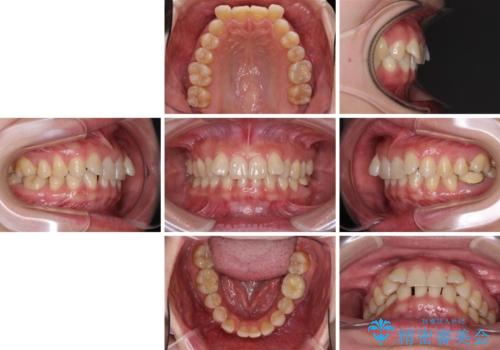

下顎2前歯の欠損 インビザラインによる抜歯矯正

- 下顎前歯欠損による歯列不正を気にして来院された患者様です。

下顎の歯列が小さく、下顎前歯が隠れてしまう過蓋咬合(ディープバイト)であったため、

①下顎歯列を拡大し、欠損部に2歯分のインプラント補綴をおこなう

②上顎左右第一小臼歯2本を抜歯、下顎歯列を拡大し、欠損部に1歯分のインプラント補綴をおこなう

③上顎左右第一小臼歯2本を抜歯し、下顎はスペースを閉じる

のいずれかを提案しました。(①から③の順番にお勧めのプランとなります)

いずれもワイヤー矯正が望ましい治療方法ですが、家が遠方であり、近い将来出産される予定もあるとのことで、何とかマウスピース矯正でも対応可能な③にて治療を行うこととしました。

マウスピースでの抜歯矯正特有の抜歯スペースに向かって奥歯が傾斜する動きが顕著に表れ、ディープバイトは改善されませんでした。

前歯のみが強く接触し、奥歯で咬めない期間も続いたため、ワイヤー装置などを補助的に使用し、何とか終了させることができました。